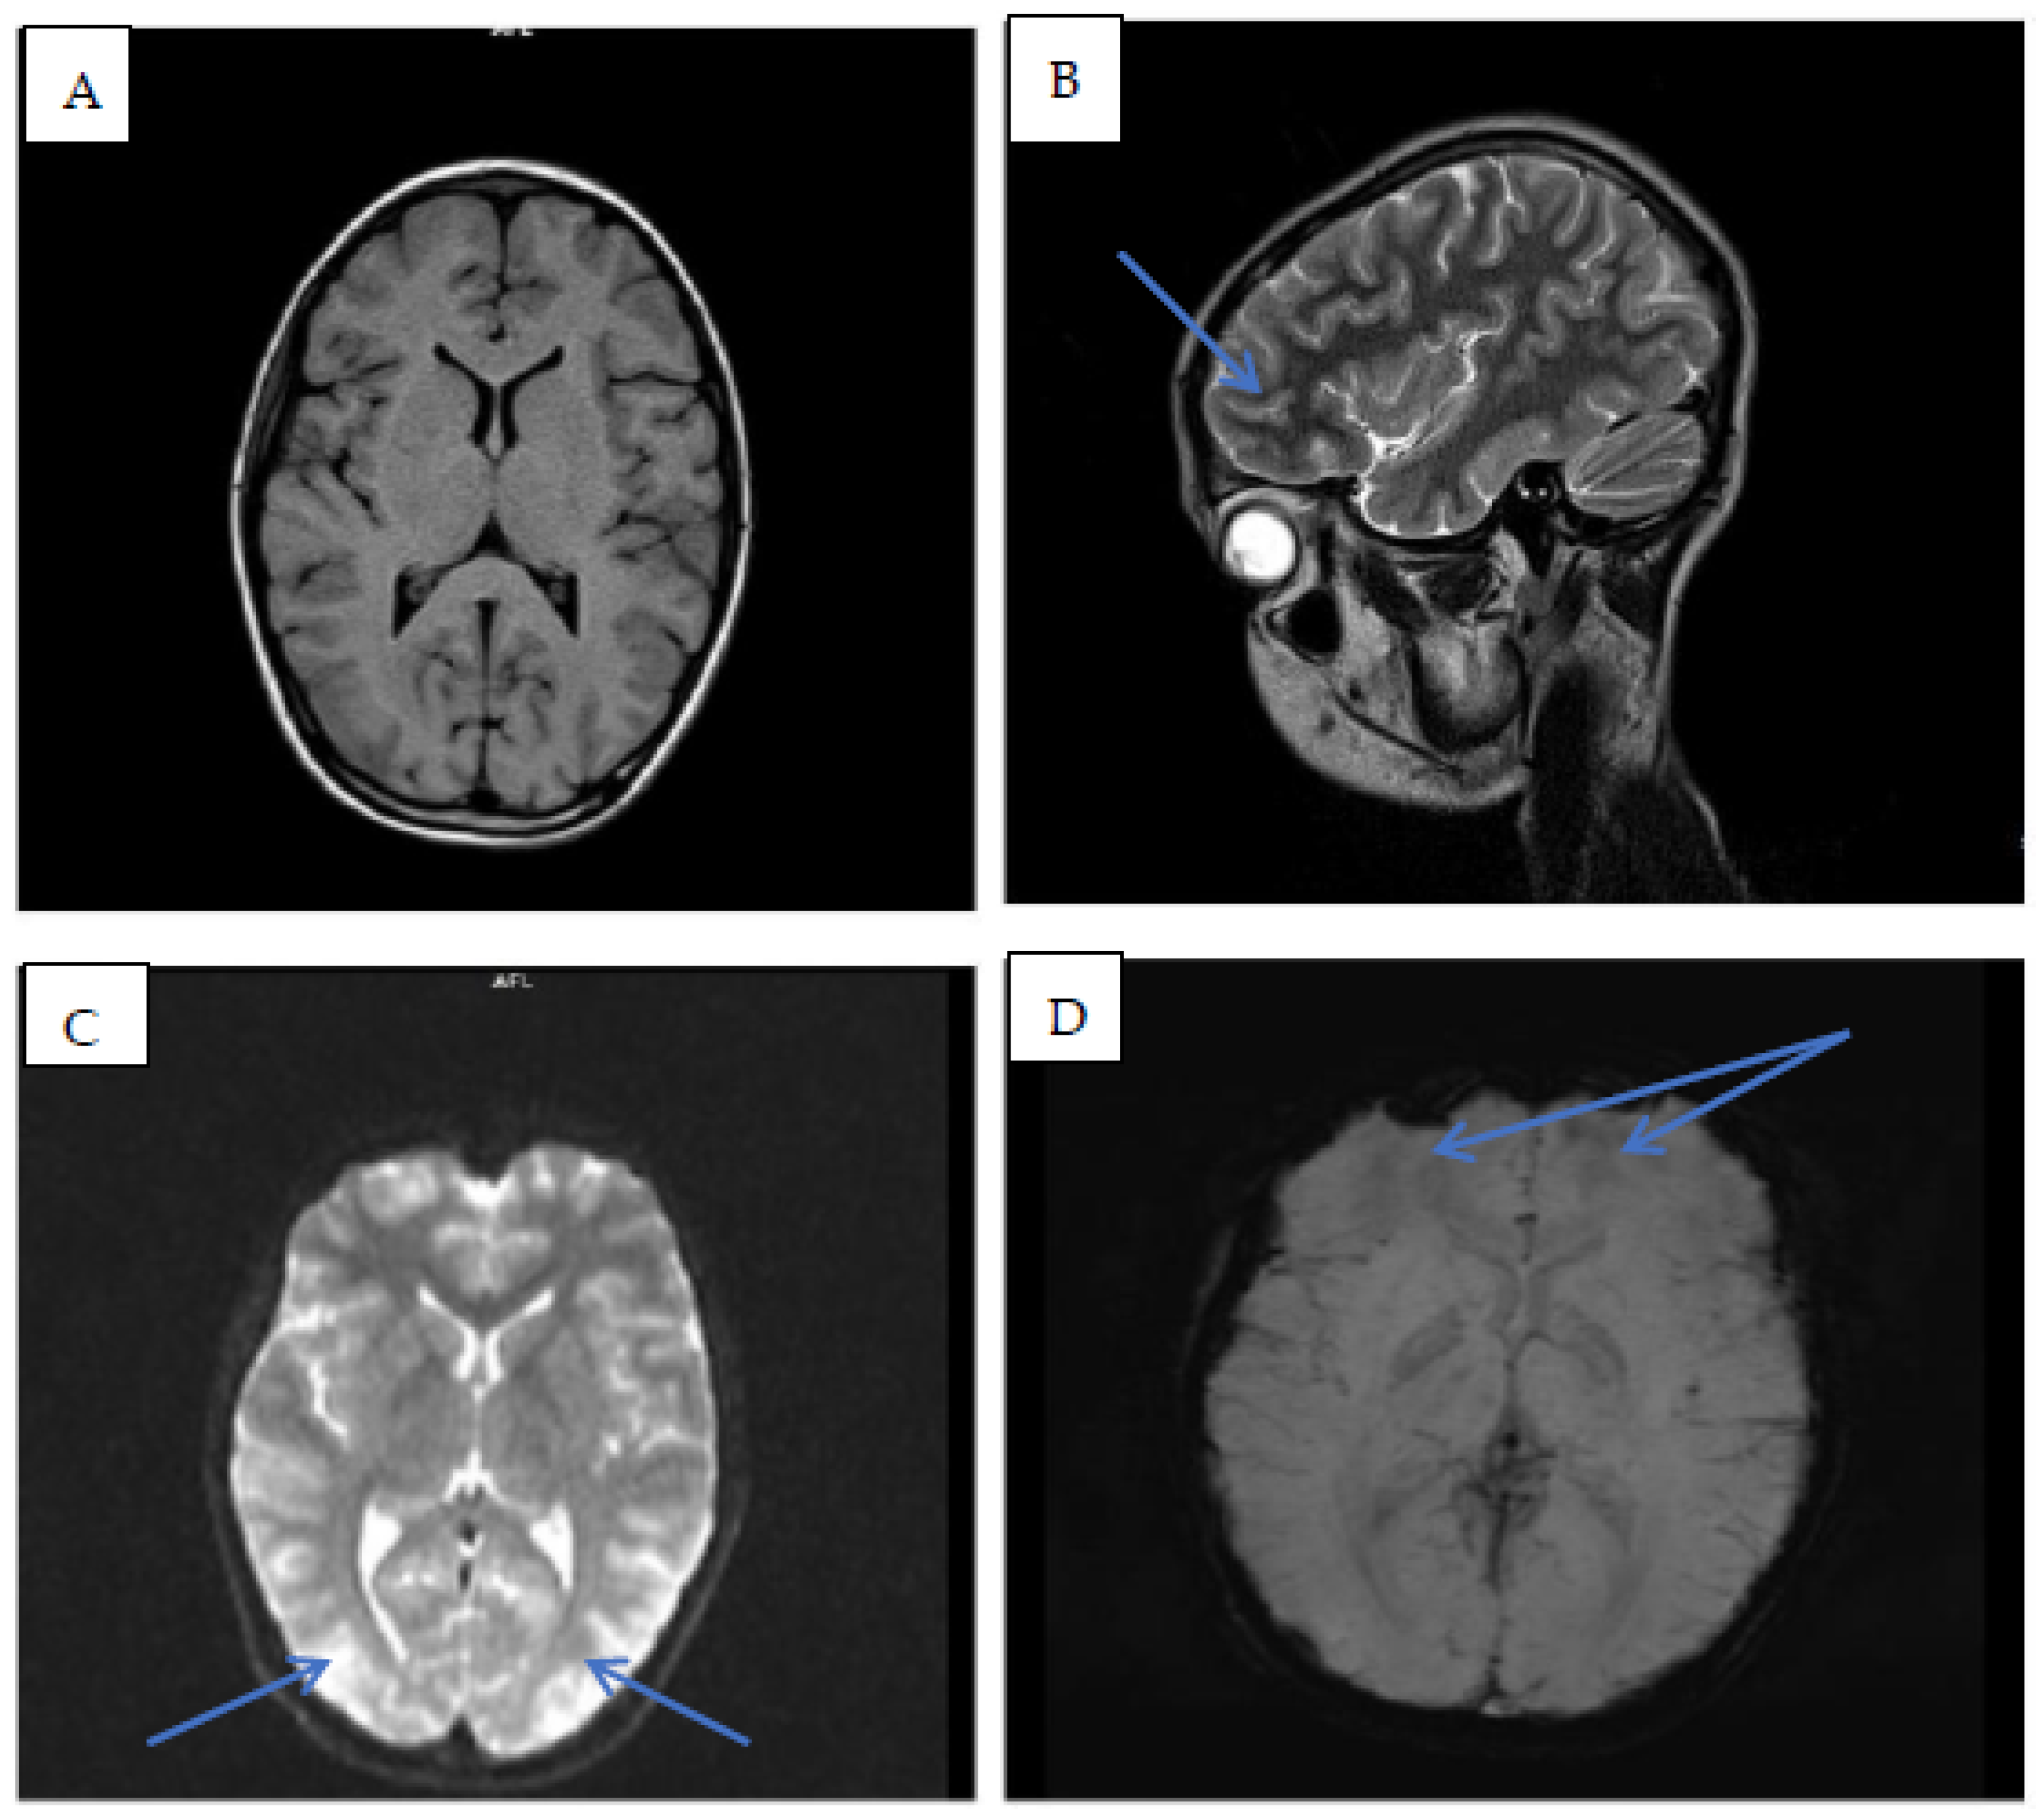

2. Patient Information

3. Follow-Up and Outcomes

4. Discussion